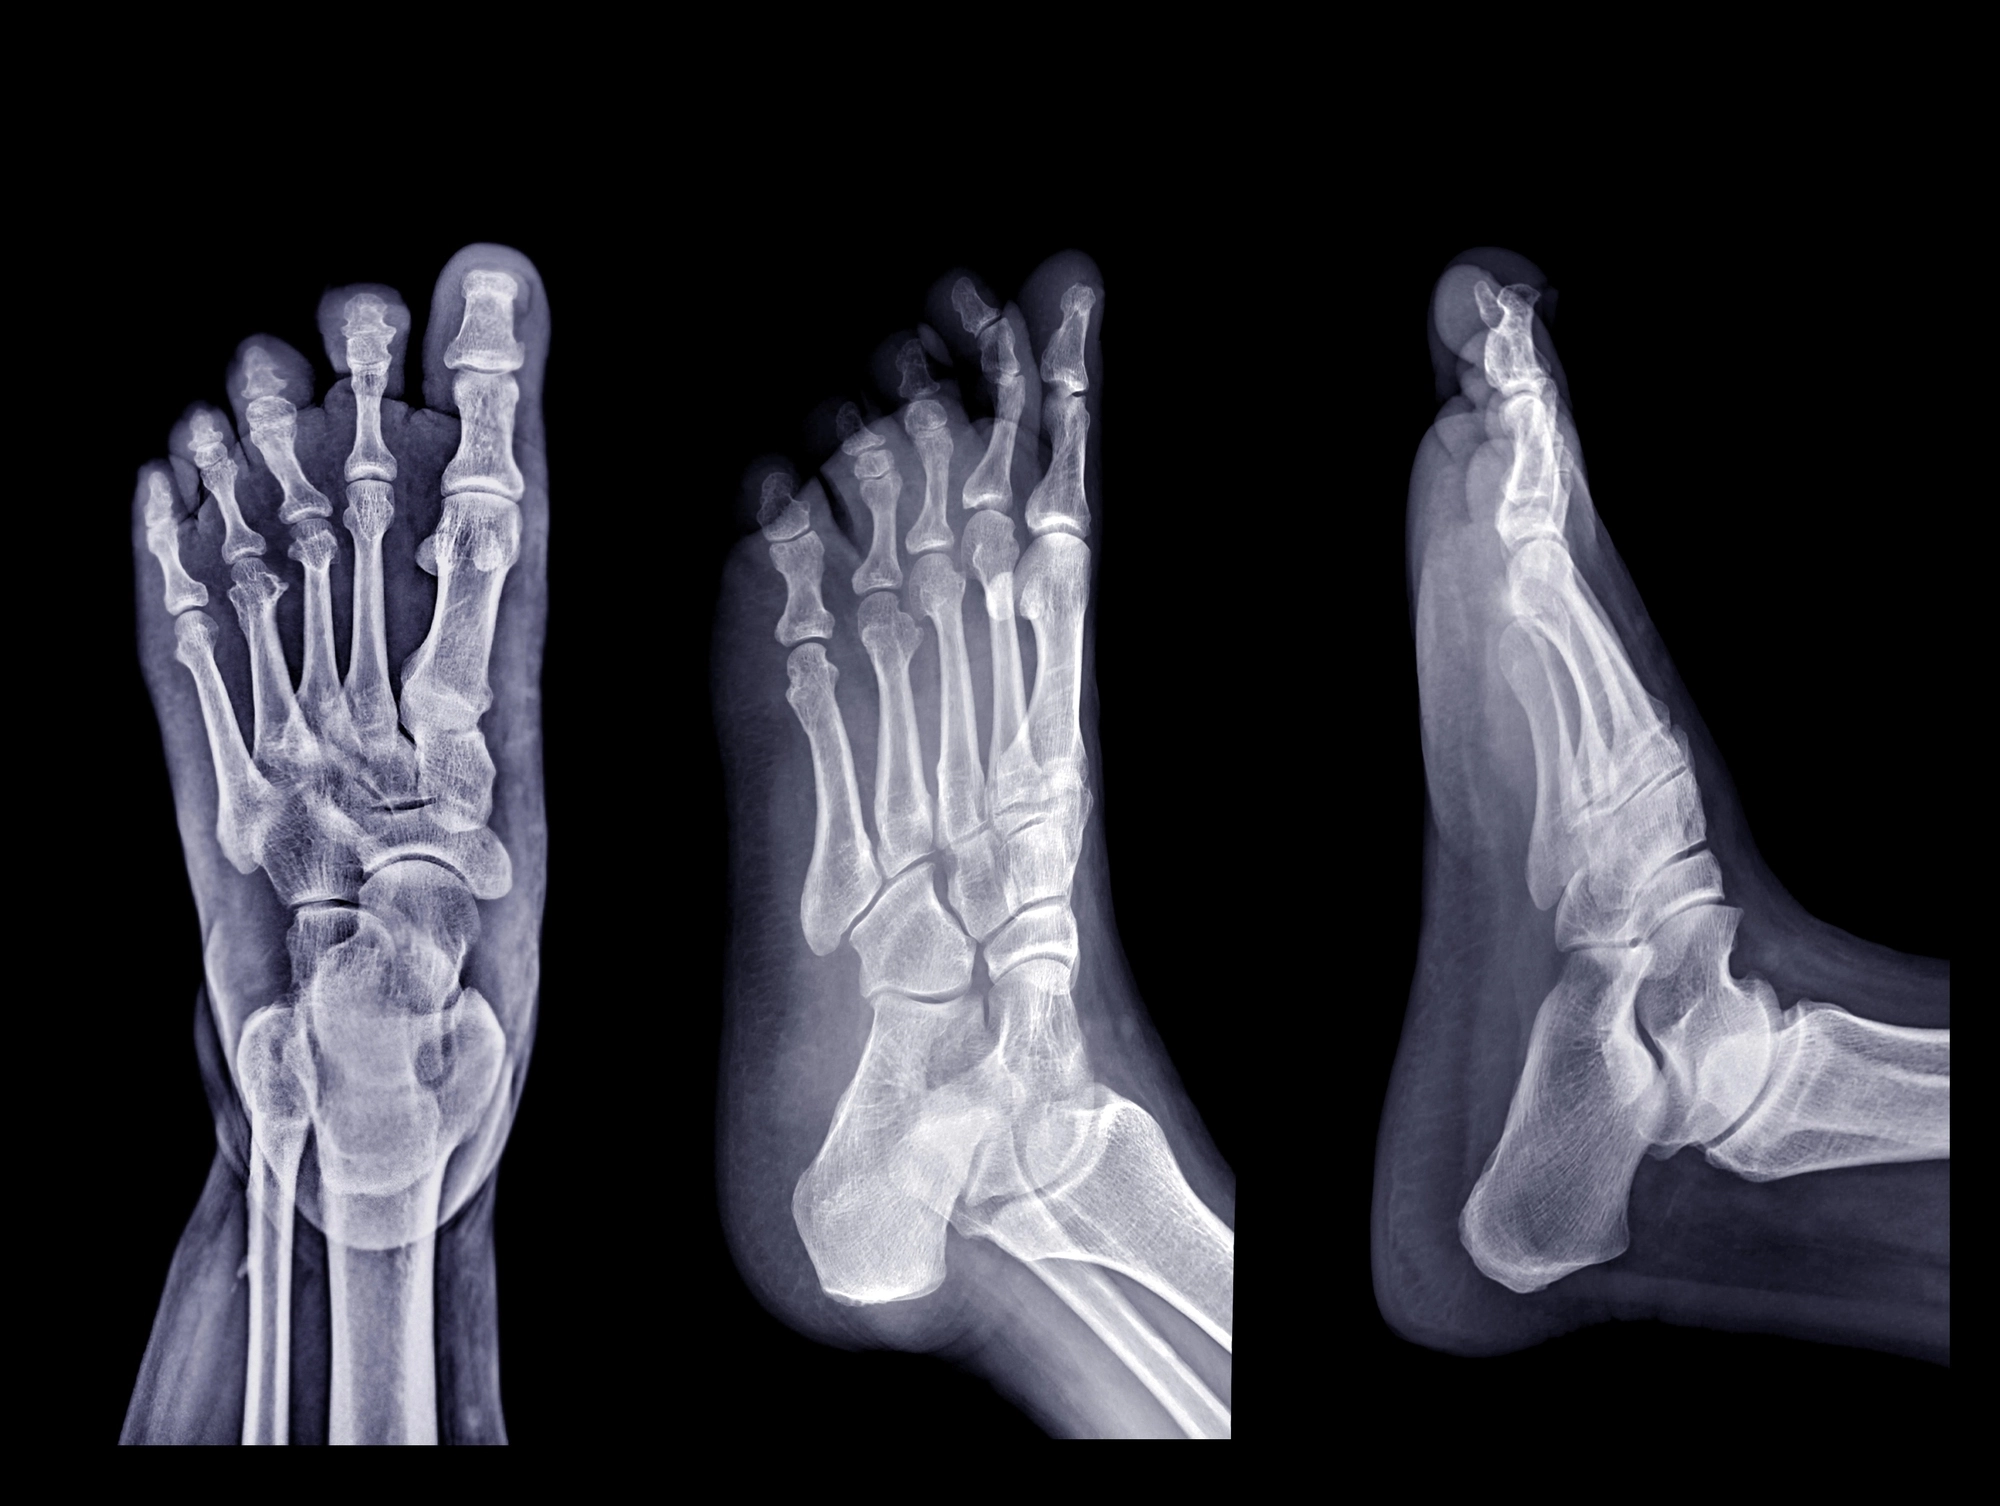

Midtarsal joint sprains are caused by ligament injuries that are responsible for holding the rear and mid-sections of the foot together. Injuries to these ligaments will cause pain, swelling, and obvious bruising in the middle or top of the foot Treatment typically involves the RICE method (Rest, Ice, Compression, and Elevation), pain management, and, for more severe cases, immobilization or surgery.

Mid-tarsal joint sprains are generally seen in athletes who play sport or activity where there is jumping and landing. The ligaments that are typically sparined and injured are the calcaneocuboid ligament and the Calcaneonavicular ligament. Part of these ligaments join together as a bifurcate ligament.